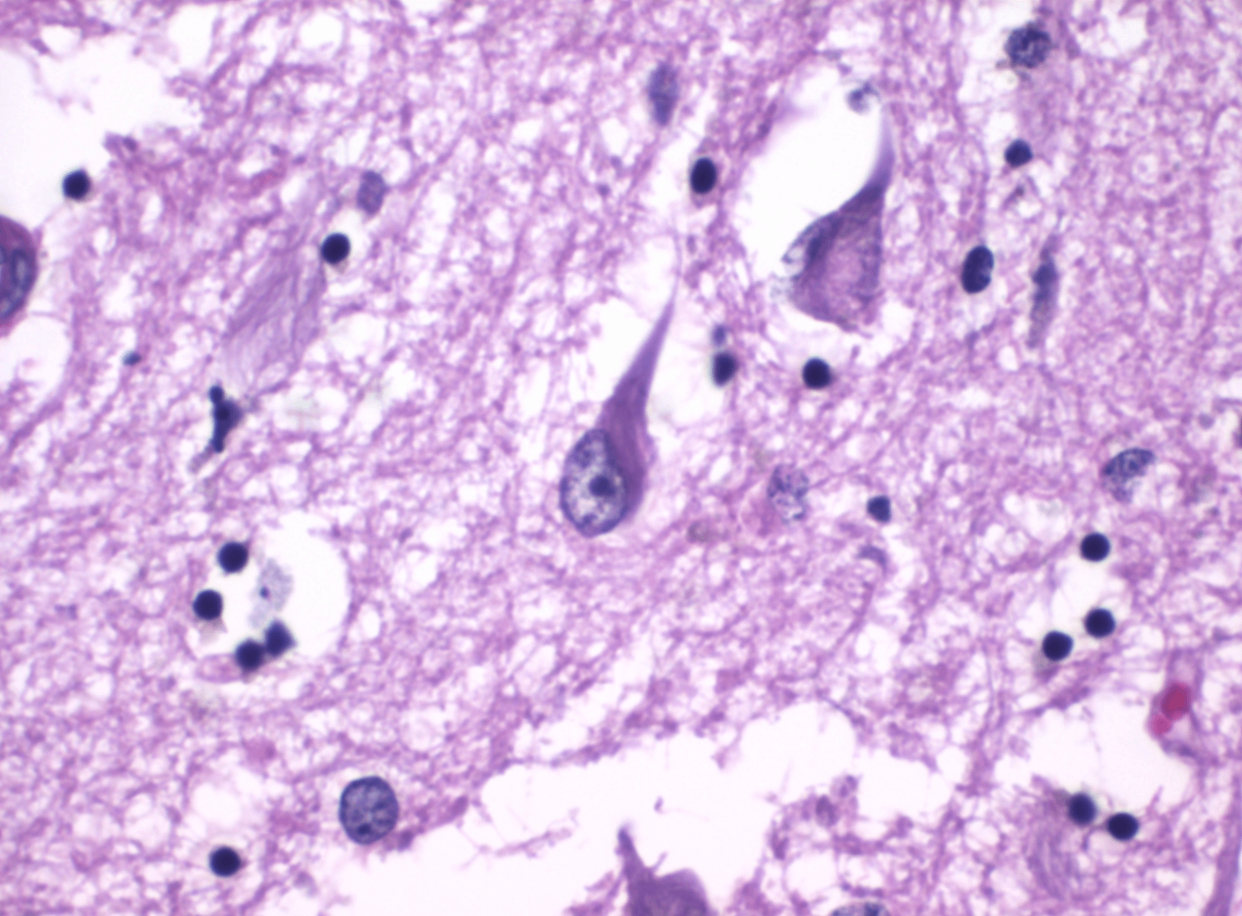

① Neuritic plaques

Aβ 플라크는 중심의 아밀로이드 핵을 중심으로, 주변이 퇴행성 신경돌기(dystrophic neurites), 반응성 미세아교세포(reactive microglia) 등 퇴행성 신경 성분으로 둘러싸여 있음

• 대뇌 피질과 해마에서 가장 흔함

Histopathology of neurofibrillary tangles in Alzheimer's disease, Wikimedia CommonsAlzheimer neuritic plaque gallyas stain, Wikimedia Commons